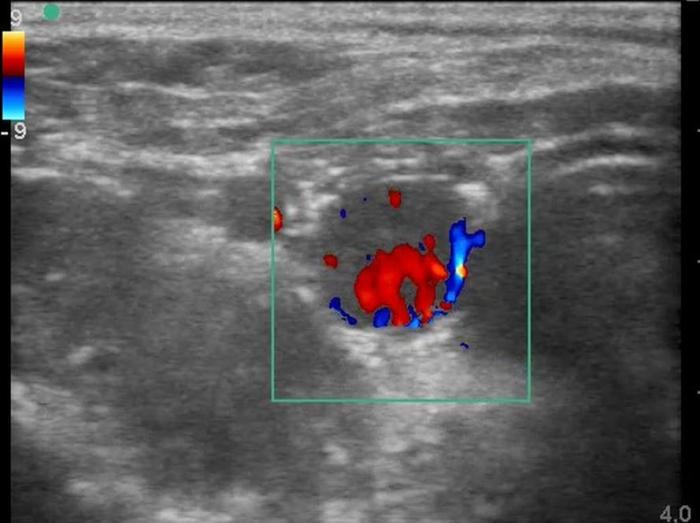

El Doppler color y espectral es especialmente útil para valorar la vascularización glandular. Un patrón de flujo periférico leve y simétrico es considerado normal. El aumento en la intensidad, desorganización o presencia de flujo central puede sugerir procesos funcionales como el hipertiroidismo o lesiones neoplásicas9.

Respecto a las lesiones nodulares, la ecografía permite diferenciar nódulos sólidos, quísticos o mixtos (Figuras 8-10), y evaluar su tamaño, forma, ecogenicidad y comportamiento vascular. La presencia de nódulos hipoecogénicos, de contornos irregulares, con vascularización central intensa y crecimiento rápido, es sugestiva de neoplasia1.

Entre las neoplasias más frecuentes se encuentran los carcinomas tiroideos, los cuales suelen presentarse como masas lobuladas, de aspecto invasivo, con pérdida de la cápsula glandular, mineralización distrófica (ver Figura 8), desplazamiento o compresión de estructuras vecinas, y vascularización anómala al Doppler13 (Figura 11A-E).

El uso del Doppler color y espectral ha enriquecido la caracterización vascular de las glándulas tiroideas y paratiroideas. La presencia de flujo central aumentado, vascularización caótica o hipervascularización periférica son signos sugestivos de actividad funcional o de transformación maligna, aunque su interpretación exige experiencia y debe ser contextualizada clínicamente4.